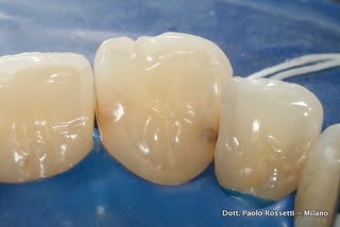

Carie interdentale su secondo premolare superiore su cui è già presente un'otturazione estesa. La carie viene asportata. Si decide di rimuovere anche la vecchia otturazione, che manifesta segni di logoramento. I restauri sui denti adiacenti vengono rilucidati.

Piccola carie interdentale su molare con vecchia otturazione. Vengono rimossi la carie e la vecchia otturazione e si esegue una otturazione in resina composita.